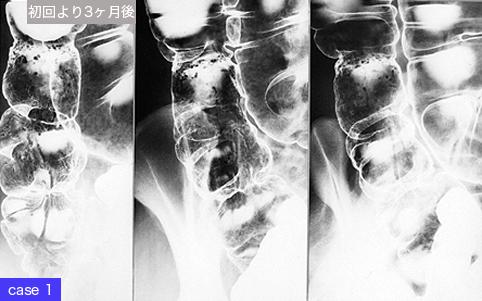

疾病(病理主体)的分类肿瘤样病变/炎症性息肉病

部位(按器官分)大肠/升结肠

检查方法X线

肿瘤最大直径1~9